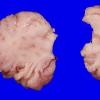

Menkes disease (4)